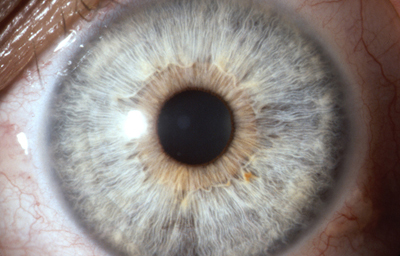

El Iris en general es muy pigmentado con colores que comúnmente van del marrón, avellana, gris, verde y azul. Existen los iris sin pigmento en el Albinismo oculo-cutáneo en cuyo caso se ven blanco/rosados.

El color del Iris es un fenómeno complejo por efectos combinados por la textura, la pigmentación y el tejido fibrovascular del estroma, junto con la constitución epigenética del individuo. Desde el punto de vista óptico, la simple absorción o reflexión selectiva por algunas moléculas, como la hemoglobina o el colágeno del estroma que son componentes no pigmentados, puede tener influencia en el color que es observado.

A pesar de la gran variedad en el color del Iris, el único pigmento que contribuye en forma sustancial es la melanina; su cantidad, es uno de los factores que determina el color del iris en una persona. Estructuralmente el color depende de la cantidad variable de eumelanina (melaninas marron/negra) y pheomelanina (melaninas rojo/amarillo) producidas por los melanocitos derivados de la Cresta Neural. El grado de dispersión de la melanina que yace en racimos subcelulares en los melanosomas, tiene cierta influencia en el color que se observa, pero el grado de dispersión no es reversible ya que los melanosomas no son moviles.

En el recién nacido el Iris es de color gris azulado por falta de migración del pigmento, el color definitivo se muestra alrededor de los 6 meses de edad.